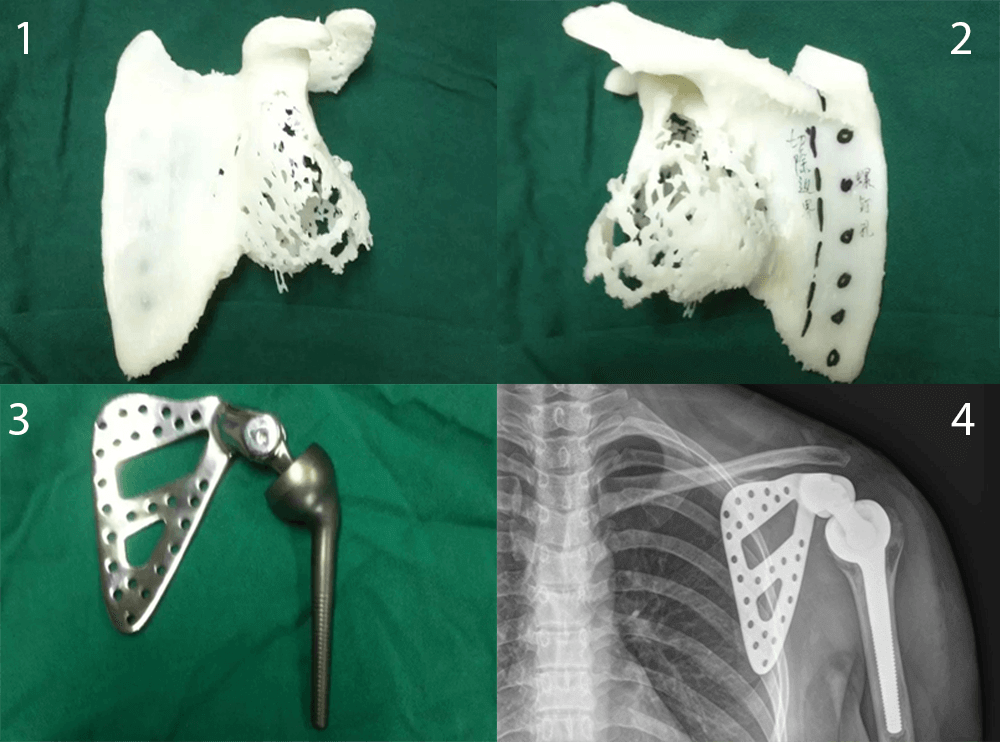

Die Bilder zeigen die Reihenfolge der Rekonstruktion des Schulterblatts. 1) Aus den Scans konnte ein Abbild des Original-Schulterblatt gedruckt werden. 2) Anpassungen für Transplantation. 3) Schulterblatt aus Titanium gemäß 3D-Druck-Vorlage. 4) Nach erfolgter Transplantation (Bild © newsgd.com).

75% des Knochens wurden durch den Tumor zerstört, wodurch sich eine operative Entfernung des Tumors erschwerte, sollte es nicht auch zu einer Amputation von Arm und Schulter kommen. Dank der 3D-Technologie war es den Ärzten aber möglich ein exaktes Replikat des ursprünglichen Schulterblatts herzustellen. Mit Hilfe verschiedener Scans wurden Berechnungen durchgeführt, die den Zustand des Schulterblatts vor dem Angriff des Tumors rekonstruieren konnten. Mithilfe eines harz-basierenden 3D-Druckers konnte eine Schablone für das Schulterblatt gedruckt werden, welche wiederum an eine andere Einrichtung geschickt wurde, um aus dieser Vorlage ein Schulterblatt aus Titanium herzustellen.

Und tatsächlich konnte vor kurzem die Operation vorgenommen werden, in der ein neues Schulterblatt mithilfe des 3D-Druckers erfolgreich in den Körper eingesetzt wurde. Die Ärzte gehen davon aus, dass Li Jieyang vollständig gesundet und schon bald wieder Arm und Schulter normal bewegen kann.